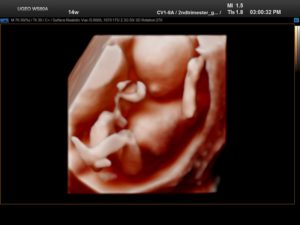

В первую очередь диагност определяет количество плодов в маточной полости и их предлежание. Если младенец занимает поперечное либо тазовое положение, на данном сроке это не является патологией.

Он активно двигается и до конца беременности примет необходимое для успешного родоразрешения предлежание. Первый триместр характеризуется ежедневными переменами в организме плода.

В начале второго триместра гестации малыш практически сформирован – он имеет вид маленького человечка, все его силы направлены на развитие мозговой активности и тела.

Ультразвуковое сканирование позволяет увидеть:

- место прикрепления плода в полости матки;

- развитие суставов;

- четкую двигательную активность – малыш плавает, кувыркается, сгибает и разгибает конечности, хватается за пуповину;

- удлинение шеи и формирование ее мышечного каркаса;

- развитие мимики лица – кроха зевает, икает, пытается гримасничать и сосать палец, реагирует на прикосновения и резкие звуки.

Этот период характеризуется началом синтеза костным мозгом клеток крови и опущения яичников в малый таз у девочек. Если же врачу удалось заметить формирующуюся предстательную железу – это свидетельствует о том, что родится мальчик. Также оценивается состояние амниотической жидкости, место прикрепления плаценты, количество сосудов в пупочном канатике (в норме их три).

Многие будущие мамы предпочитают пройти 3д-сканирование – его принцип основан на таком же способе, как и обычное УЗИ, однако трехмерное изображение позволяет выявить пороки сердца и аномалии развития центральной нервной системы. Качественный снимок УЗИ в 14 недель позволяет разглядеть пропорциональное тело крохи, намечающийся волосяной покров на головке, брови и реснички, заметить выражение личика крохи и сходство с родителями.